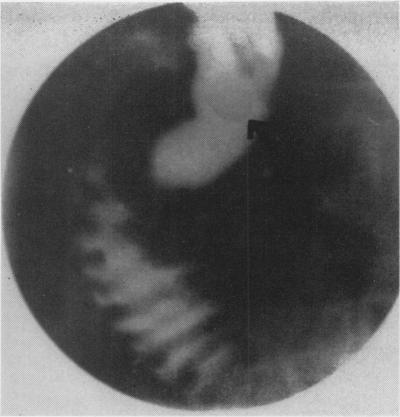

Residual common duct calculi.

Ann Surg. 1956 May;143(5):619-26; discussion, 626-7. doi: 10.1097/00000658-195605000-00008.